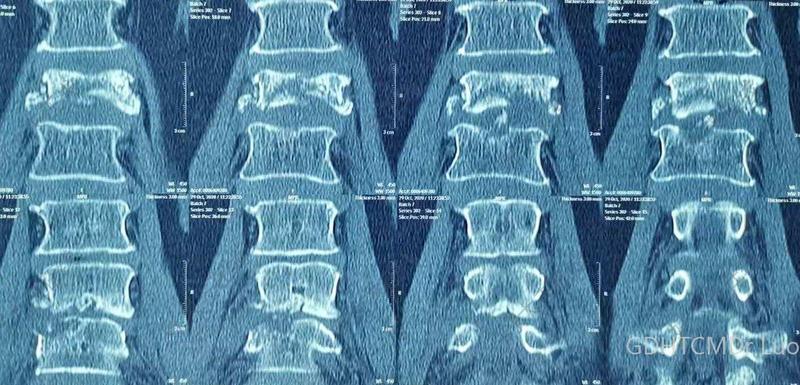

腰椎術(shù)后翻修

治療前1.外院3月前第一次行后路L3/4椎板擴(kuò)大減壓術(shù);2.術(shù)后右下肢仍有疼痛,肌力下降;難以坐起;3.復(fù)查腰椎MR、CT感染可能性大治療后治療后13天1.術(shù)式:后路L3-5椎弓根釘固定+病灶清除+椎間植骨融合術(shù);2.術(shù)中未見明顯膿性組織,椎間隙髓核基本缺失,未見明顯死骨;3.術(shù)后病理未見腫瘤、結(jié)核、感染組織等;術(shù)中多次細(xì)菌培養(yǎng)未見細(xì)菌生長;4.診斷:感染?依據(jù)?其他?5.術(shù)后情況:右下肢痹痛減輕,仍乏力,戴腰圍坐起可。